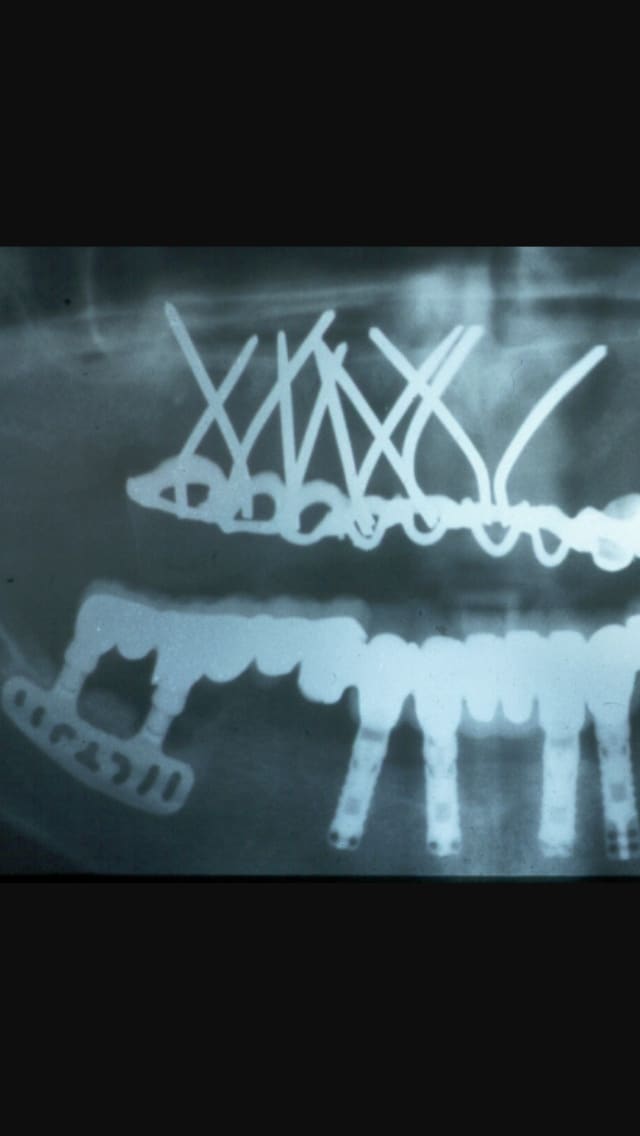

Fallait avoir un certain niveau pour placer ce genre d'implants et avoir peur de rien

faut s'appeler scortecci ou shoffler ))))

je susi emeerveillé par ce qu'ils sont arrivés a faire sans l'aide des scan etc